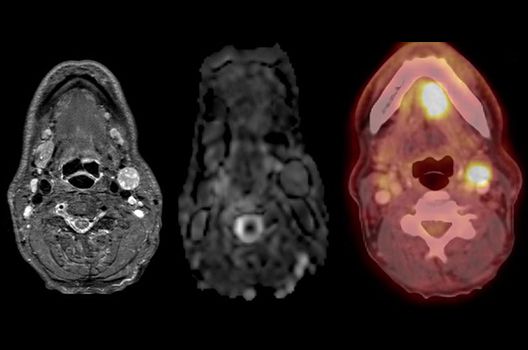

Die Hybridbildgebung mittels PET/MRT spielt insbesondere in der onkologischen Bildgebung eine wichtige Rolle. Eine mögliche Fragestellung ist die Unterscheidung zwischen einem Tumorrezidiv oder therapeutisch assoziierten Veränderungen insbesondere dann, wenn diese Frage mittels MRT alleine nicht beantwortet werden kann.

Die bildgebende Diagnostik und Verlaufsbeurteilung von Tumoren des Nervensystems ist einer der klinischen und Forschungsschwerpunkte unserer Abteilung. Eine besondere Bedeutung kommt der Hybrid-Bildgebung zu. Das Universitätsklinikum verfügt über einen integrierten Ganzkörper-PET/MRT-Scanner, der die Vorteile der MRT-Bildgebung und der Positronenemissionstherapie (PET) vereinigt. Aufgrund der langjährigen klinischen Arbeit und Forschungstätigkeit mit diesem Gerät hat die Neuroradiologie Tübingen maßgeblich zur Etablierung dieses Verfahrens beigetragen. Auch weiterhin forschen wir intensiv an neuen Methoden zur frühen Einordnung von Tumoren und insbesondere Tumorrezidiven, die mit anderen Methoden häufig nicht erfasst werden können.